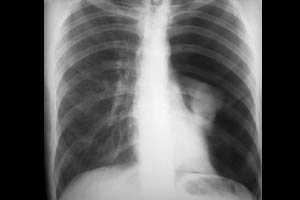

Ателектаз при проведении ИВЛ может иметь свой причиной как неправильное стояние эндотрахеальной (трахеостомической) трубки — ее расположение в одном из главных бронхов (чаще в правом), так и закупорку главного или долевых бронхов сгустками мокроты. Все это приводит к гиповентиляции или полному отсутствию вентиляции перекрытых отделов бронхолегочного дерева. Ателектаз проявляется ослаблением дыхания над пораженным участком, а также характерной рентгенологической картиной. Лечение ателектаза заключается в устранении его причины и дальнейшем продолжении ИВЛ.

Вентилятор-ассоциированная пневмония является поздним осложнением механической вентиляции легких. Она обычно развивается начиная с третьи суток пребывания пациента на ИВЛ. Как правило, вентилятор-ассоциированная пневмония вызывается внутрибольничной флорой реанимационного отделения, а отсюда плохо поддается стандартной антибактериальной терапии. Наиболее частые возбудители: клиебсиелла, ацинетобактер, золотистый стафилококк. Диагностика вентилятор-ассоциированной пневмонии проводится на основании клиники (стойкая лихорадка, аускультативная картина), лабораторных данных, рентгенологической картины. Обязателен посев мокроты и определение чувствительности выделенной культуры к антибиотикам. Лечение заключается в назначении эмпирической, а затем и прицельной антибактериальной терапии, обычно состоящей из антибиотиков резерва. Эффективно также назначение антибиотиков и антисептических средств ингаляционно.

При планировании отлучения пациента от искусственной вентиляции лёгких прежде всего необходимо оценить его компенсаторные резервы и способность к самостоятельному дыханию. Для начала процедуры отлучения пациент должен быть полностью стабилен в плане дыхания, гемодинамики, состояния внутренней среды организма, устранения основных очагов инфекции. В частности, очень важны такие критерии, как достаточный уровень сознания, положительная клинико-рентгенологическая динамика патологии легких, нормализация податливости лёгочной ткани, снижение сопротивления дыхательных путей, адекватная нервно-мышечная проводимость, нормоволемия. Важно, чтобы у пациента было компенсированное состояние кислотно-щелочного равновесия и водно-электролитного баланса. Параметры оксигенации также должны быть хорошими.